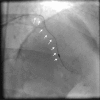

Figure 3.

Figure 3.. Long and angulated left anterior descending artery with calcification (arrows) and an entrapped burr after the angulation.